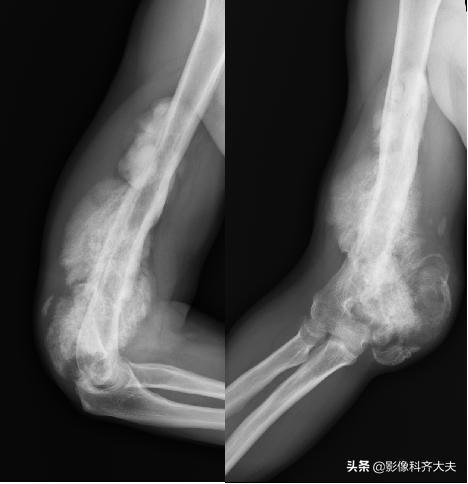

肱骨远端骨折后大量骨痂形成,骨小梁穿越骨折处

骨化性肌炎:

肌腱韧带损伤时,骨膜撕脱或剥离,形成骨膜下血肿。一个月左右血肿钙化或骨化。

X线表现为骨旁软组织内出现不规则的片条状或团块状钙化或骨化影,一年后可完全吸收,或遗留一小骨块影。

因有外伤史可与骨旁骨瘤、骨软骨瘤、皮质旁软骨瘤等鉴别。